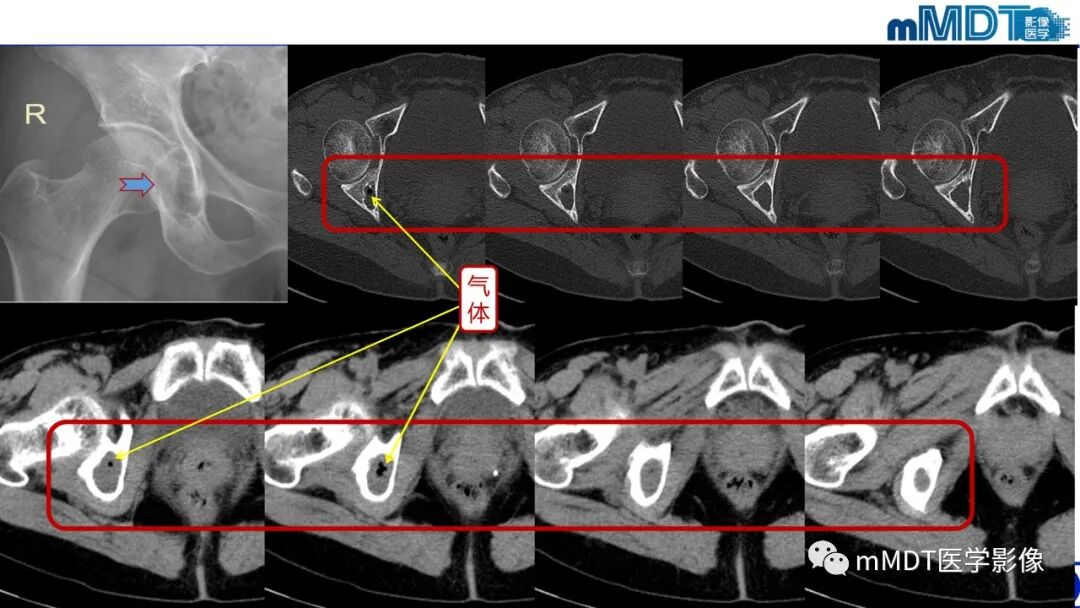

髂腰肌撞击

髂腰肌撞击症它是导致腹股沟区疼痛的常见原因之一。髂腰肌撞击症相关盂唇损伤直接位于前方,位置位于3点钟方向。

自体髂腰肌撞击原因尚不明确,可能机制有三个:

(1)髂腰肌肌腱过紧或存在炎症,对股骨头和盂唇产生的撞击和摩擦导致盂唇损伤;

(2)髂腰肌肌腱与前方关节囊盂唇复合体粘连,二者间的接触摩擦导致反复的牵拉损伤。髂腰肌肌腱与滑囊间的慢性炎症,造成纤维粘连,屈伸髋关节过程中对关节囊盂唇复合体的反复牵拉导致盂唇损伤。

(3)髂小肌对髋关节前方盂唇的过度摩擦,导致盂唇损伤。髂小肌起自关节囊前方与髂耻隆突,止于股骨小粗隆远端,是髋关节前方的稳定结构。在髋臼发育不良或髋关节不稳定患者中,该肌肉会代偿性肥大,导致关节囊紧张并对盂唇过度摩擦,导致盂唇损伤。